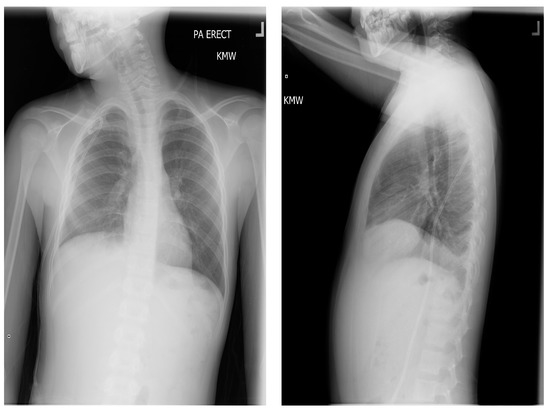

Figure 4.

Pre-operative chest X-rays obtained about 1 month after initial presentation, with pigtail chest tube and persistent right chylous effusion (based on imaging and persistent chylous output from chest tube).